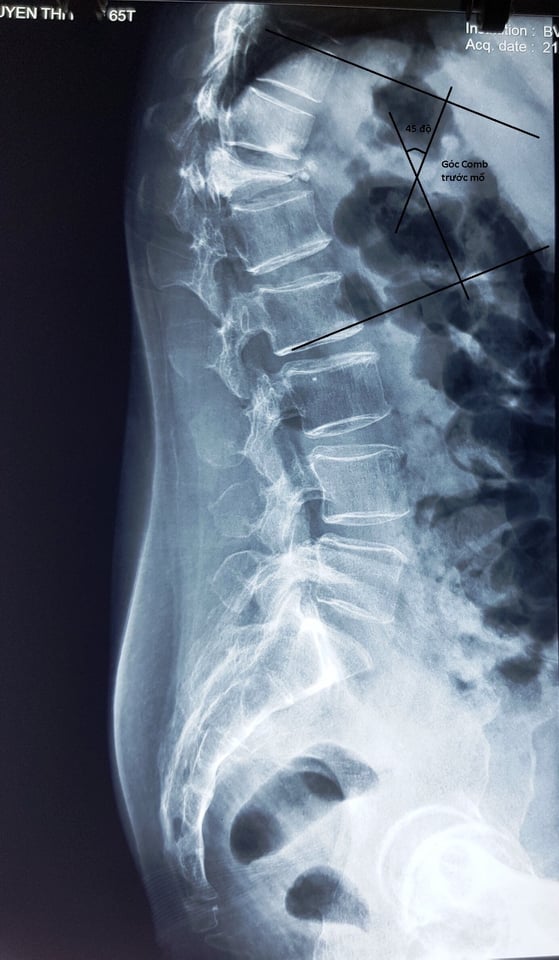

Bệnh nhân Nguyễn Thị NG 64 tuổi bị chấn thương vùng cột sống ngực nhiều tháng nay, sau chấn thương bệnh nhân đau nhiều vùng cột sống nhưng không đi khám và điều trị. Thời gian gần đây bệnh nhân đau nhiều, đau ngày càng tăng, yếu hai chân, gù cột sống, đi lại khó khăn, rối loạn cảm giác vùng bẹn, đùi. Bệnh nhân đến khám tại bệnh viện đa khoa Sơn Tây được khám và chụp phim XQ, cộng hưởng từ phát hiện bị vỡ xẹp nặng thân đốt sống ngực T 12, có mảnh xương vỡ từ thân đốt sống chèn vào tủy sống. Kíp phẫu thuật của Bệnh viện đa khoa Sơn Tây đã hội chẩn với chuyên gia về phẫu thuật cốt sống BS.Phan Minh Trung (Bệnh viện Thanh Nhàn). Bệnh nhân đã được phẫu thuật kết hợp xương nẹp vít thân đốt sống mở cung sau giải ép thần kinh. Ca phẫu thuật thành công, sau mổ bệnh nhân hết rối loạn cảm giác vùng bẹn đùi, hai chân đỡ yếu và sẽ phục hồi theo thời gian, chụp XQ hết gù cột sống.